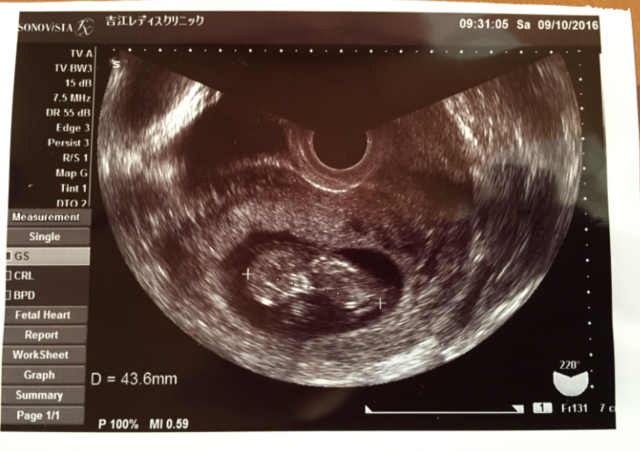

10週3日(10w3d・性別不明)|なぁひろ さん(20歳)

エコー写真撮影時のエピソード:

前回卵みたいな形だったのが初めて頭や足が見えて、ちゃんと成長したのが目に見えて分かって、愛おしく思えた。鉄分を取るようにしたり、葉酸のタブレットを買ったり、好きだったお寿司や生物を食べないように気をつけるようになった。パパもエコー写真を見て父親の自覚が出てきた。